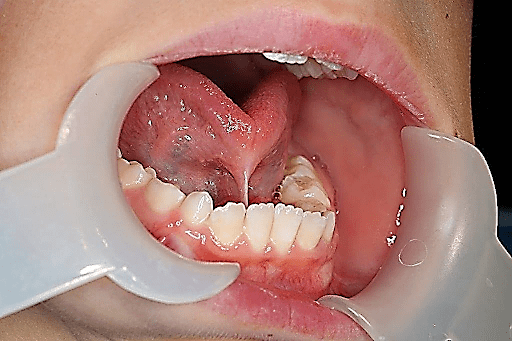

Test for frenum surgery

High lingual Frenum